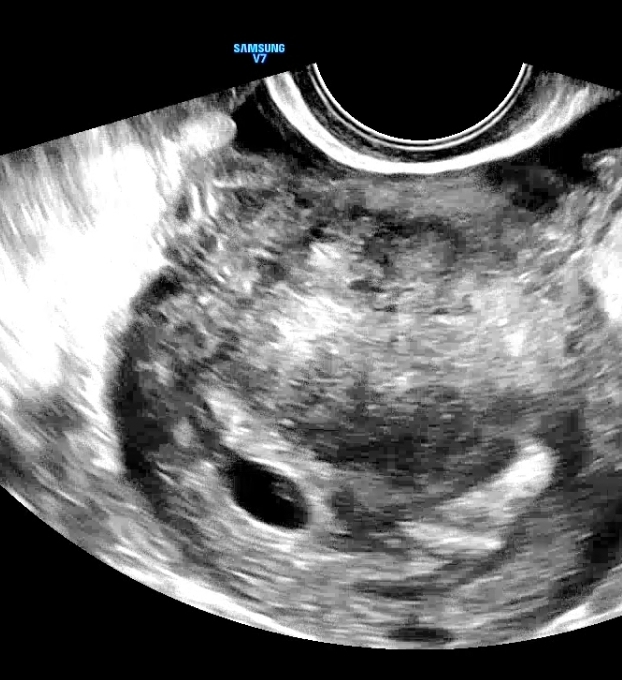

시험관주수 6주 4일 / 예상주수 6주1일 심장박동 확인

난황은 조금 작아진 느낌이고 아기집은 아주 조금 커진 느낌

아기는 이틀사이에 0.29 -> 0.46 로 조금 컸다 ㅠㅠ

아뮤튼 촘파는 같은병원에서 잰게아니라 정확도는 좀 떨어지는듯 화질차이도 좀 있고 이병원에서는 난황자체가 잘 안보였다

그리고 피고임도 많다고 하셨다